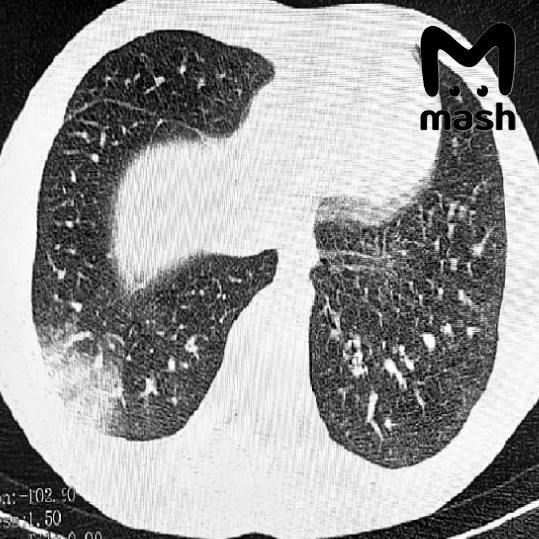

Подростки в тяжёлом состоянии, одному пришлось делать операцию на лёгких.У 16-летнего пациента — серьёзная дыхательная недостаточность, потребовалась искусственная вентиляция лёгких. У другого — двусторонняя вейп-ассоциированная пневмония EVALI, врачи...